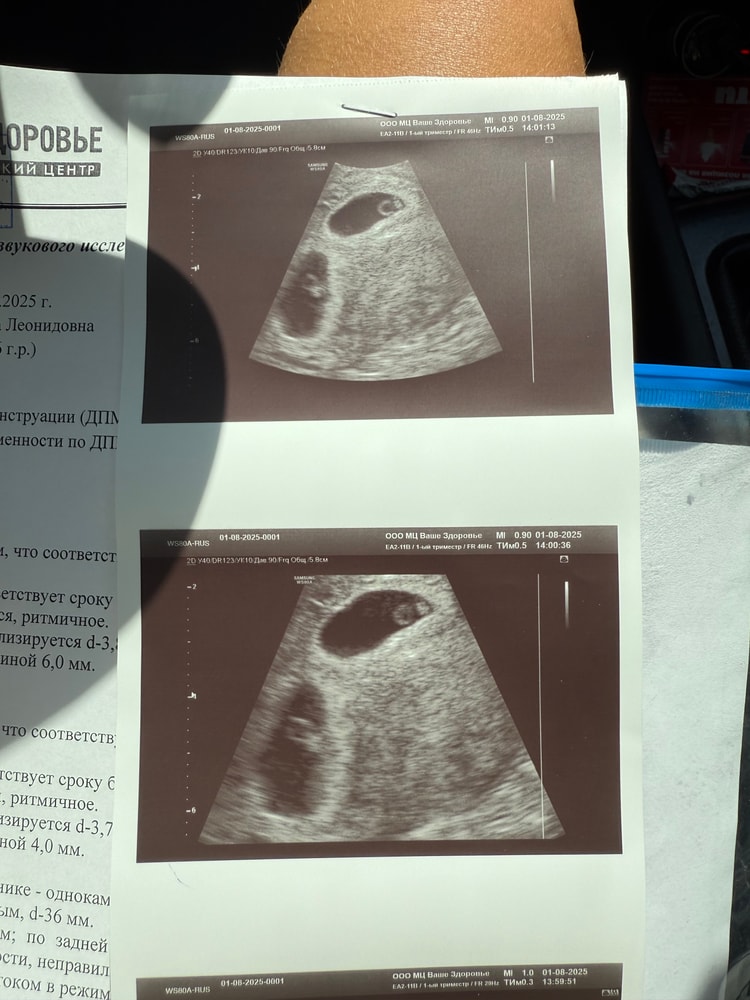

Мама двоих (2 месяца, 2 месяца)

Севастополь

Сумайя, спасибо ! Немного страшновато, но мы очень рады❤️ 8 лет бесплодия💔